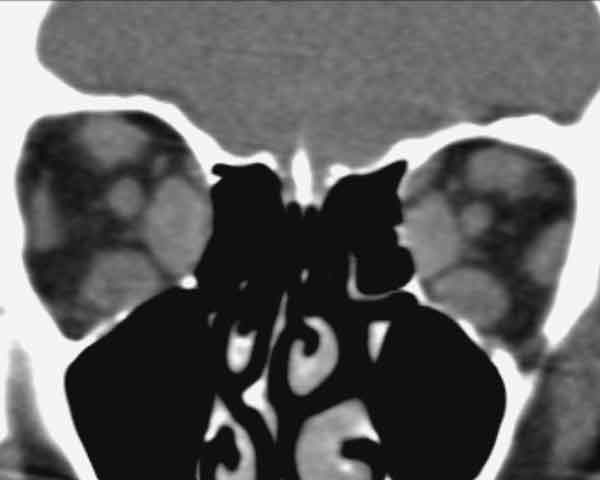

L’orbitopatia tiroidea colpisce colpita una donna ogni 6 mila, in eta’ compresa tra i 35 e i 60 anni. I dati, che si riferiscono agli Stati Uniti, sono simili alla situazione italiana, dove non esistono ancora statistiche ufficiali. Di questo argomento endocrinologi, radiologi ed oculisti ne parleranno confrontandosi per la prima volta sulle novita’ relative al trattamento della orbitopatia tiroidea, un disturbo che causa alterazioni importanti nell’orbita oculare.

L’occasione viene dal convegno “Oftalmopatia Basedowiana”, che si svolgera’ sabato 29 maggio a Fiano (Torino), vuole puntare i riflettori su una delle conseguenze piu’ frequenti, ma anche poco conosciute, delle alterazioni a carico della funzionalita’ della tiroide, in particolare del morbo di Graves. Secondo uno studio condotto dal Dipartimento di Oftalmologia della Mayo Clinic di Rochester nel Minnesota nel 1995 e pubblicato sull’American Journal of Ophthalmology, ci sono 16 nuovi casi ogni 100mila abitanti all’anno per quanto riguarda le donne, mentre la percentuale si abbassa a tre nuovi casi ogni 100mila abitanti l’anno per i maschi con un rischio 85% maggiore per le femmine. Nelle donne il picco d’eta’ di incidenza e’ tra i 40 e i 44 anni e tra i 60-64 anni, mentre per gli uomini dai 45 ai 49 e dai 65 ai 69. “Il problema colpisce soprattutto le giovani donne che, in pochi mesi, possono ritrovarsi con gli “occhi in fuori” – afferma Francesco Bernardini, chirurgo oculoplastico organizzatore dell’evento insieme a Renata Migliardi, oculista di Torino, ed Ezio Ghigo, direttore della cattedra di endocrinologia delle Molinette di Torino -. Si tratta di alterazioni importanti che compromettono in modo significativo l’estetica, e che possono intaccare anche la vista e le funzioni oculari. A soffrirne sono soprattutto le persone con una familiarita’ per le malattie della tiroide e le conseguenze sull’occhio sono piu’ gravi nei fumatori, e sembrano essere anche dose-dipendente; piu’ sigarette si fumano e piu’ e’ grave la manifestazione oculare”.Quasi sempre le pazienti affette richiedono un trattamento per la riabilitazione estetica, cioe’ hanno il desiderio di ritornare come prima della malattia e cio’ non e’ quasi mai raggiungibile con farmaci, steroide o altro. Nel convegno si parlera’ di importanti novita’ riguardanti il trattamento dell’orbitopatia tiroidea, che consentono di risolvere il problema in modo mini invasivo e senza complicazioni.